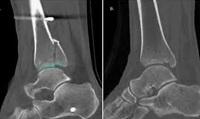

Las fracturas complejas de tobillo frecuentemente afectan el maléolo posterior. Existen numerosas clasificaciones que describen las fracturas maleolares posteriores (FMP). El objetivo de este estudio fue realizar una revisión sistemática de la literatura para describir las clasificaciones de FMP existentes y estimar su precisión. Ver más…